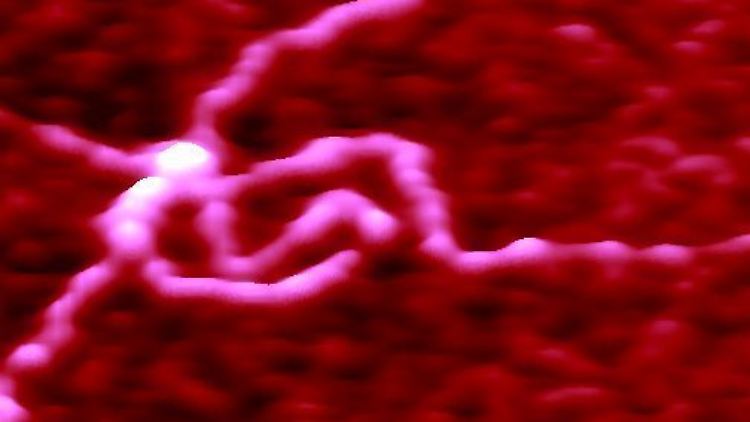

Sich kreuzende DNS-Stränge, aufgenommen mit einem Rasterkraft-Mikroskop. Bei der Untersuchung zum Miller-Syndrom zeigten sich in einem DNA-Abschnitt gehäuft Fehler.

(Foto: picture-alliance / dpa)

Die Exome der beteiligten Probanden wurden mit schnellen Automaten gelesen und am Computer miteinander verglichen. Theoretisch hätte man dieses Verfahren schon lange anwenden können, aber erst die drastisch beschleunigte Sequenzierungstechnik macht dies auch praktisch möglich. Dabei zeigten sich in einem DNA-Abschnitt gehäuft Fehler, betroffen war ein Gen namens Dihydroorotat-Dehydrogenase (DHODH). Das aus ihm hervorgehende Enzym ist in der Zelle an der Produktion von Pyrimidin beteiligt. Dieses ist ein Grundbestandteil der Nukleinsäuren, die genetische Information in der DNA codieren.